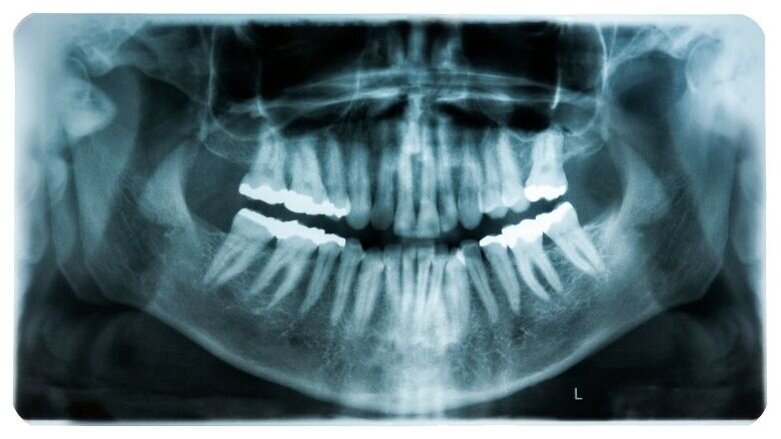

BERLIJN, DUITSLAND – Tandartsen van de Charité-Universiteitskliniek in Berlijn hebben in samenwerking met datawetenschappers en programmeurs dentalXrai Pro ontwikkeld: een softwareprogramma dat tandheelkundige beoefenaars de mogelijkheid geeft om de analyse van röntgenfoto’s uit te voeren op basis van artificial intelligence (AI). De nieuwe software is ontworpen om tandartsen te helpen om aandoeningen en restauraties accurater en in minder tijd te identificeren en zo in een optimale behandeling te voorzien en de communicatie met patiënten te verbeteren.

Aangezien de meeste tandartspraktijken al digitale röntgenfoto’s maken, kunnen deze gemakkelijk doorgegeven worden aan dentalXrai Pro. Om in zeer korte tijd een vooraf geanalyseerde foto te leveren, maakt de browsersoftware gebruik van high-performance computers en een omvangrijke reeks algoritmes.

Deze algoritmes zijn het resultaat van een diepgaande softwaretraining waarbij een zeer grote dataset van tandheelkundige röntgenfoto’s is gebruikt, waaronder panoramische en bitewingfoto’s. Tandartsen wereldwijd identificeerden tienduizenden pathologische veranderingen en sporen van eerdere tandheelkundige behandelingen in de röntgenfoto’s. Deze data werden vervolgens doorgezet naar de kunstmatige netwerken, waardoor zij verschillende bevindingen van elkaar konden onderscheiden, zoals cariës, infecties en wortelkanaalvullingen.